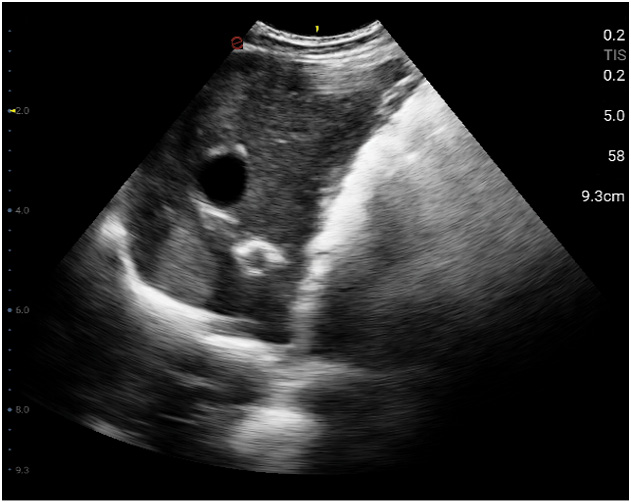

Esaote Q7 Vet er et trådløst, håndholdt ultralydapparat dedikert for veterinærer. Spesialtilpassete forhåndsinnstillinger og software og database designet for dyr. Esaote Q7 kombinerer kraften til moderne ultralydteknologi med brukervennlighet og mobilitet.

Med håndholdt ultralyd og en smartmobil/nettbrett, kan du gjøre raske og gode undersøkelser med Esaote Q7. Dets trådløse design gjør det mulig å utføre ultralydundersøkelser av høy kvalitet når som helst og hvor som helst. Alt er tilrettelagt for en vellykket undersøkelse.